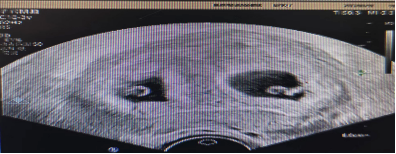

NT检查:12周后检测婴儿背部的透明带;